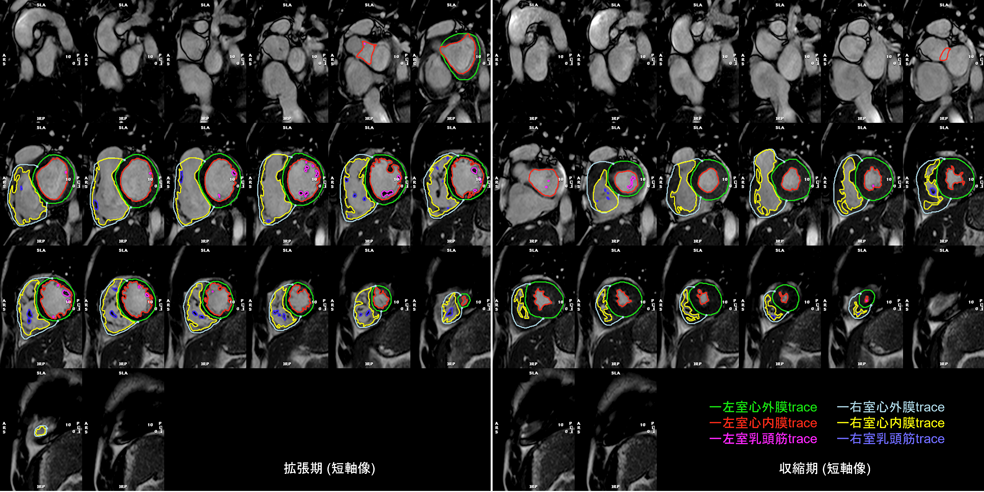

心室全体をカバーする単軸像すべてに対して,心外膜と心内膜の輪郭をトレースすることで,内腔容積を算出する.短軸像を積み重ねることで心室全体の容積が算出できる.拡張末期と収縮末期の両時相において内腔容積を計測することで,拍出量や駆出率などが算出される(Fig. 8).

Fig. 8 Left ventricular (LV) and right ventricular (RV) chamber quantification. For LV chamber quantification, the endocardial (red) and epicardial (green) contours are delineated in diastole (left) and systole (right) in a stack of short axis slices that cover the whole left ventricle. For RV chamber quantification, the endocardial (light blue) and epicardial (yellow) contours are delineated. Papillary muscles and cordal tissues are excluded from the LV and RV volume.

左右心室の拡張末期・収縮末期のタイミングが一致している場合は,左室の計測を行った後に同じ時相(画像)で右室の心内膜・心外膜トレースを行うことができ,心室中隔部分のトレースを省けるため簡便である(心室中隔は左室に含まれる)(Fig. 8).